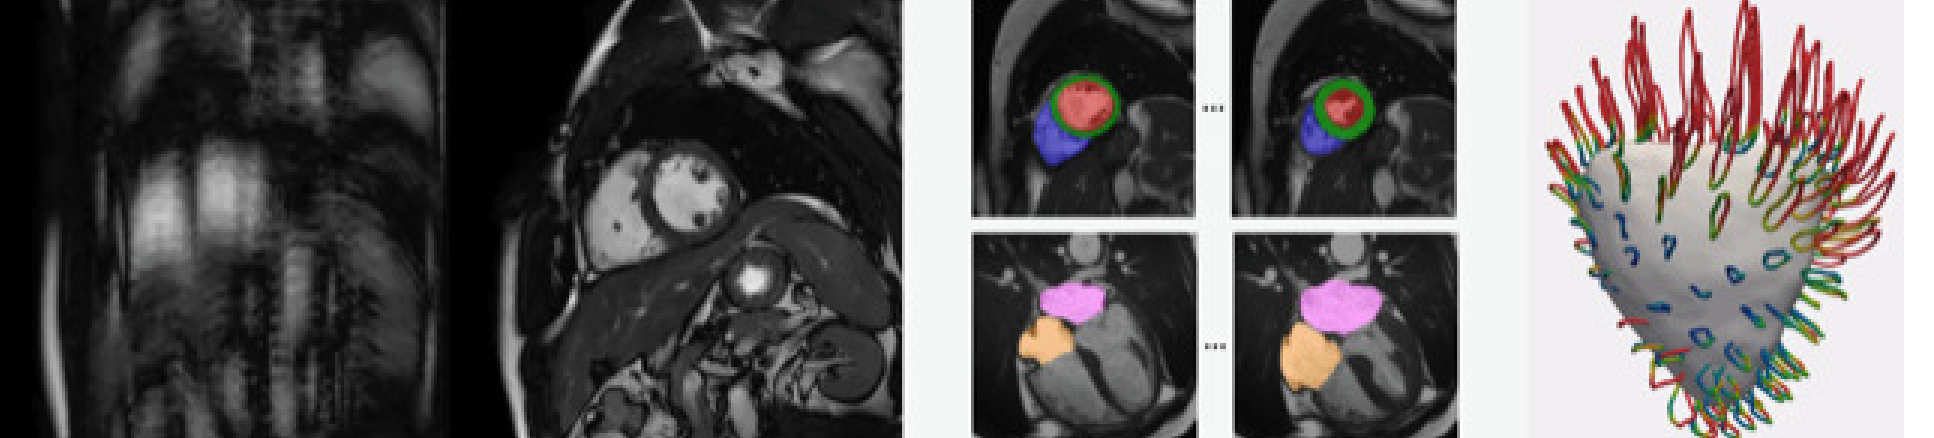

Professor Daniel Rueckert is aiming to use artificial intelligence (AI) to achieve better quality medical images in shorter times. The project will also aim to automate the interpretation of the images in an objective fashion.

Professor Rueckert, Head of the Department of Computing, will integrate AI, in the form of machine learning, into all stages of the medical imaging pipeline, ranging from image acquisition and reconstruction to analysis and interpretation.

The project's primary focus will be on cardiovascular imaging, for patients with heart disease, and fetal/neonatal imaging to identify neurodevelopmental abnormalities.

Professor Rueckert will integrate AI into all stages of the medical imaging pipeline

"By integrating AI into medical imaging, we will be able to acquire better quality medical images with richer information in shorter times.

“This has the potential to reduce costs, increase efficiency and patient-friendliness as well as to provide higher diagnostic and prognostic accuracy for clinical decision making.”